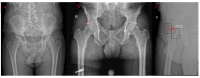

Figures